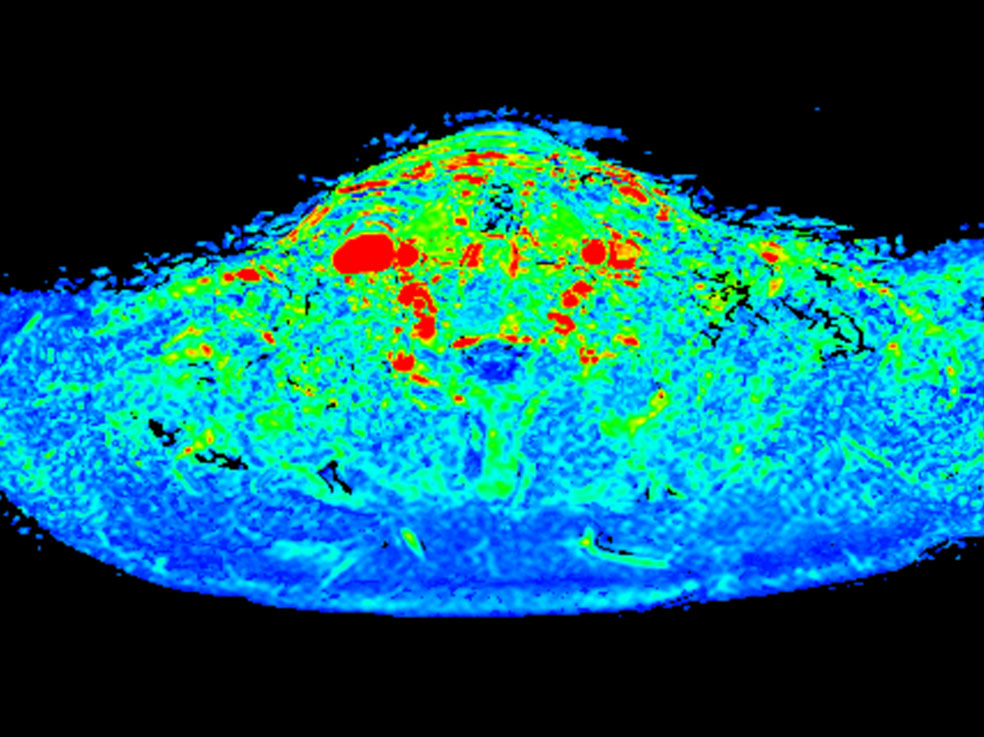

Axial T1w mDIXON XD FFE (max enhancement)